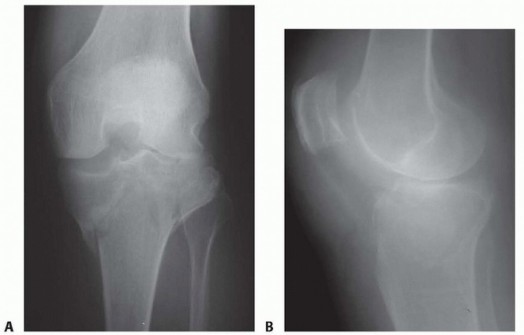

DEFINITION Bicondylar tibial plateau fractures involve both medial and lateral tibia plateaus. Schatzker type…